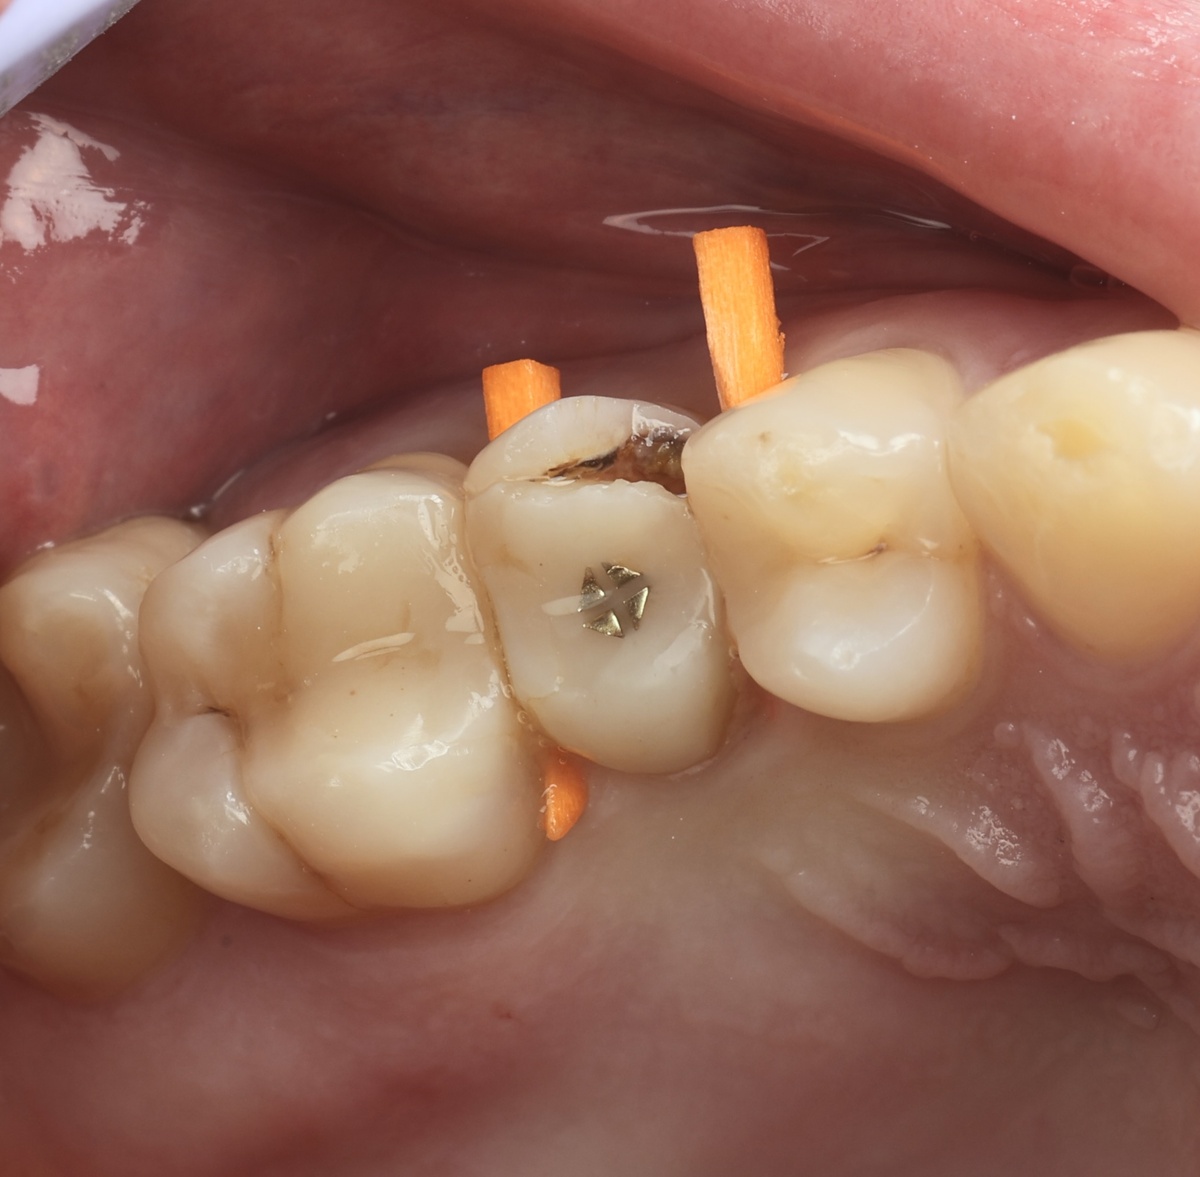

Зуб 2.5 до лечения

Поражение оказалось сильным - три стенки из четырёх разрушены ниже уровня десны, периодонтит.

Убрали старые пломбы:

Убрали старые пломбы

Извлекли анкерный штифт:

Извлекли анкерный штифт

И стало видно, насколько плохи дела. Разрушение стенок критичное, корень в уровень с десной, практически. Но даже это - не приговор. Врачу удалось установить коффердам и матрицы, удалось обеспечить герметизм: